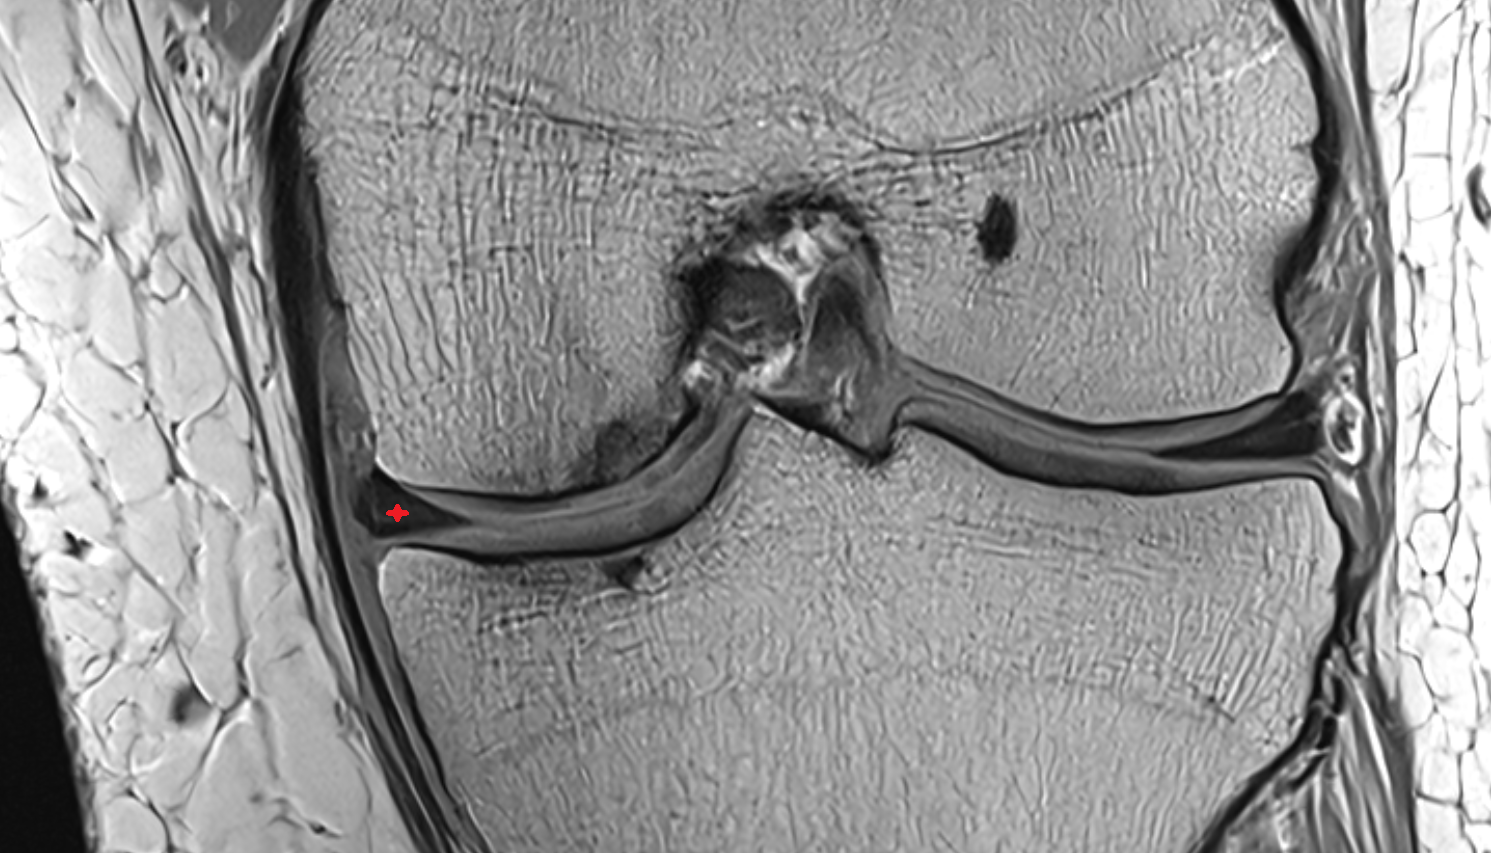

- Medial collateral ligament

- Anterior cruciate ligament

- Posterior cruciate ligament

- Medial meniscus

- Lateral meniscus

- Posterior horn of medial meniscus

- Posterior horn of lateral meniscus